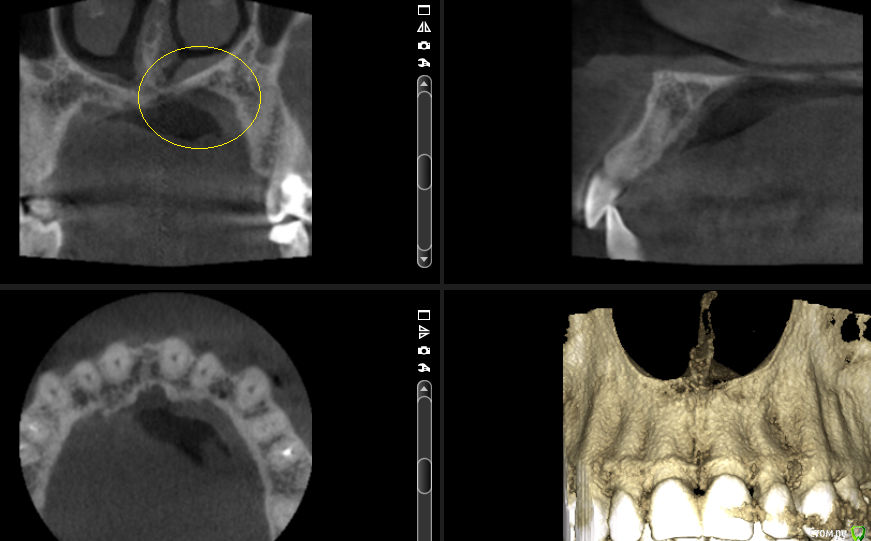

___49___ Опубликовано 19 сентября, 2016 Поделиться Опубликовано 19 сентября, 2016 (изменено) Уважаемые коллеги прошу высказать свое видение предоставленных срезов КТ ...Основной диагноз : Нейропатия второй ветви левого тройничного нерва.Из анамнеза: Пациентка отмечает появление болей (усиливающиеся при движениях левым глазом) в супро, -инфроорбитальной области после лечения 26 го зуба 3 года назад. Неэффиктивность НПВС. Мне не нравится область твердого неба по ходу одноименного нерва : увеличенный свод с диффицитом костной ткани с участками полного ее отсутствия , незначительное утолщение слизистой в верхнечелюстной пазухи и полости носа напротив выше обозначенного участка . . мысли идут в сторону деструктивных изменений связанных с пат.изменениями нервной ткани второй ветви тройничного нерва . . поделитесь своими мыслями .... Изменено 19 сентября, 2016 пользователем ___49___ 2 Ссылка на комментарий

kriokov Опубликовано 20 сентября, 2016 Поделиться Опубликовано 20 сентября, 2016 . поделитесь своими мыслями .... не видно ни деформации костной ни деструкции костной. Залейте в файлообменник папку с DICOM фалами , ссылку в тему. Будет время, можно покрутить, может мысли какие и посетят 1 Ссылка на комментарий

___49___ Опубликовано 21 сентября, 2016 Автор Поделиться Опубликовано 21 сентября, 2016 Спасибо за альтернативное видение (чтение) кт . Если вариант Криокова или Воффа верный - то нужно как то объяснить изменения в прилегающей к данной области слизистой ...? Я залил на файлообменник все срезы из папки IMAGES , СТ - файлы. http://www.fayloobmennik.net/6575763 Ссылка на комментарий